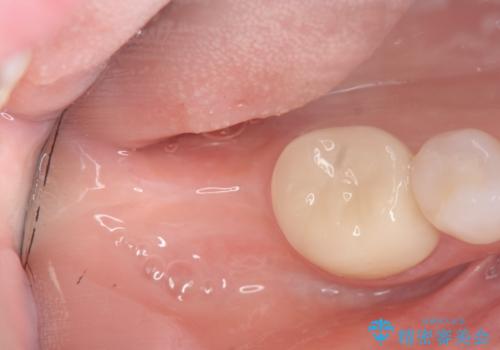

奥歯のインプラント治療

- 右下の奥歯を虫歯で喪失しそれ以来よく物が噛めず、改善を求めて来院されました。

入れ歯かインプラント治療のご提案を行い、よりしっかりとかめるインプラント治療を希望されました。

骨との結合する期間が早く、大きな咬合力にもしっかりと耐えることのできるストローマンインプラントを用いた咬合機能回復を計画します。

- 44万円(ストローマンインプラント・チタンカスタムアバットメント・仮歯・フルジルコニアクラウン)費用は治療当時の料金となります